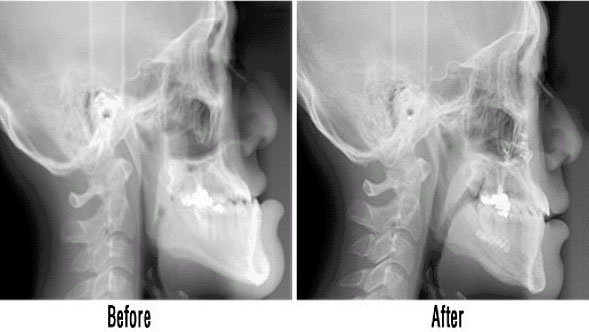

주걱턱의 턱교정 수술은 저작 및 발음 등 기능상 문제와 V라인 얼굴형을 만드는 심미적인 두 부분이 모두 충족되어야 수술 후 만족도가 높아질 수 있다.그러나 기능적인 부분을 고려하지 않고 외적으로 보여지는 심미적인 부분에만 목적을 둔 경우 수술 자체를 후회하는 경우를 종종 볼 수 있다.따라서 턱교정 수술 전 전문의 선택이 매우 중요하다고 할 수 있다.

주걱턱 수술은 각 개인마다 턱의 돌출된 정도와 치열의 모양에 따라서 그 방법이 달라지게 된다.아래턱을 뒤로 넣는 수술·위턱과 아래턱을 동시에 넣는 수술·돌출된 턱 끝을 다듬어 주는 수술이 있으며,치열교정도 환자의 상태에 따라 선교정과 후교정이 다르게 결정된다.